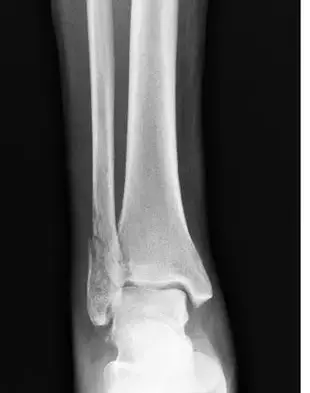

الأشعة السينية هي الخيار الأولي والأساسي لتقييم الكتف. على الرغم من أنها توفر معلومات محدودة حول الأنسجة الرخوة المحيطة بالكتف، إلا أنها ضرورية للكشف عن الكسور وتقييم العظام، وتحديد علامات التكلسات أو التغيرات التنكسية في المفاصل. يجب أن تتكون سلسلة صور الكتف من صورتين متعامدتين على الأقل لتوفير رؤية شاملة للمفصل والهياكل المحيطة به.

عند تقييم إصابات الكتف، هناك عدة صور شعاعية أساسية يجب أخذها في الاعتبار:

- صورة أمامية خلفية حقيقية (Grashey view): يتم التقاط هذه الصورة بوضع المريض مستقيماً أو جالساً أو مستلقياً مع تدويره بزاوية 30-45 درجة بالنسبة لجهاز التصوير. هذه الصورة مهمة لتقييم مفصل الكتف الحقاني العضدي (Glenohumeral joint)، والكسور (في العضد القريب والترقوة والكتف والأضلاع)، وهجرة العضد القريب. تعتبر هذه الصورة مثالية لتقييم المسافة بين رأس عظم العضد والحق، مما يساعد في تشخيص حالات عدم الاستقرار أو الخلع الجزئي. كما أنها تسمح بتقييم دقيق لحواف الحق، مما يساعد في الكشف عن وجود كسور أو تشوهات.

- صورة أمامية خلفية (AP view): يتم التقاط هذه الصورة بوضع المريض مستقيماً أو جالساً أو مستلقياً مع توجيه الشعاع بشكل عمودي على الجسم. تسمح هذه الصورة برؤية الكتف في وضعه التشريحي، وتعتبر مفيدة بشكل عام لتقييم الوضع العام للعظام.

- صورة المحور الإبطي (Axillary view): تُظهر هذه الصورة علاقة رأس العضد بالتجويف الحقاني بشكل أفضل، وتُستخدم للكشف عن الخلوع الأمامية أو الخلفية للكتف، والكسور في التجويف الحقاني، وتحديد موقع الأجسام الغريبة. قد يكون من الصعب إجراؤها في حالات الألم الشديد.